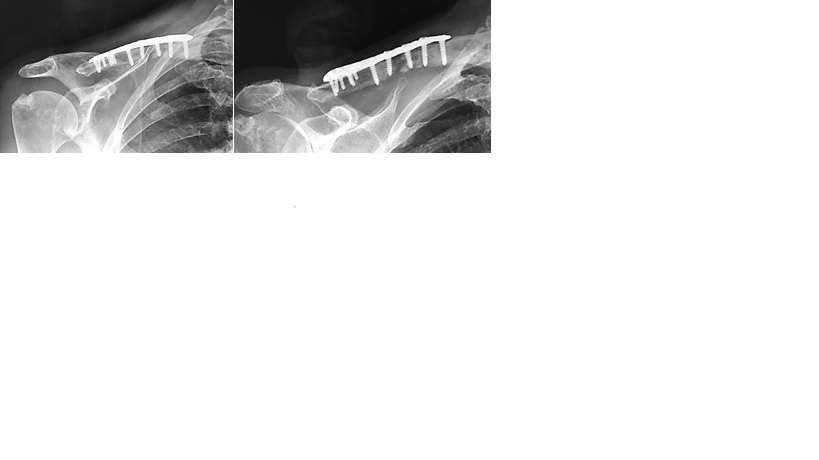

La pseudoartrosis de clavícula es una causa infrecuente de síndrome de opérculo torácico. En el presente artículo describimos un caso de plexopatía braquial por pseudoartrosis previamente infectada de clavícula en el cual se realizó claviculectomía total para el alivio de los síntomas. Realizamos una revisión bibliográfica del tema. Escasos artículos han sido publicados. Del análisis de la literatura citada concluimos que la claviculectomía total es una opción a ser tenida en cuenta cuando se han agotado las opciones terapéuticas. Los resultados funcionales pueden ser satisfactorios cuando la indicación es por infección, plexopatía o por sarcoma. AbstractClavicle non-union is an uncommon cause of thoracic outlet syndrome. A case of brachial plexopathy by previously infected clavicle pseudarthrosis is described. Total claviculectomy was performed for symptom relief. From literature analysis we conclude that total claviculectomy is an option to be taken into account when therapeutic options have exhausted.Functional results could be adequate when total claviculectomy is indicated in cases of infection, plexopathy or sarcoma.Descargas